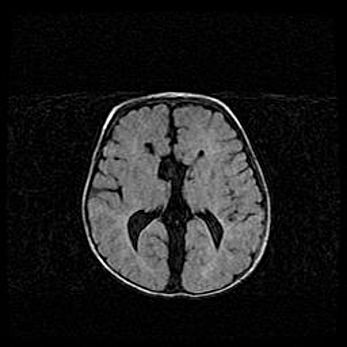

Открытая гидроцефалия.

Возраст: 6 месяцев 15 дней

Вес: 6200 г

Пол: женский

Окружность головы: 41 см

Срок гестации: 38 недель

Гидроцефалия головного мозга у новорожденных – это скопление избыточного количества цереброспинальной жидкости в головном мозге. Ее избыточное скопление в мозге приводит к патологическому расширению желудочков мозга (четырех полостей, расположенных в глубине белого вещества мозга, заполненных цереброспинальной жидкостью и связанных узкими проходами).

Открытый тип гидроцефалии (сообщающаяся) наблюдается тогда, когда нарушен механизм всасывания ликвора в системный кровоток. При этом типе причиной заболевания чаще всего является перенесенные ранее инфекции (например: менингит),  либо же наличие крови в субарахноидальном пространстве.